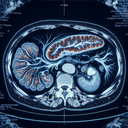

МРТ органів черевної порожнини – це неінвазивний метод діагностики, що використовує магнітне поле та радіохвилі для створення детальних зображень внутрішніх органів і структур черевної порожнини. Це дослідження часто застосовується для оцінки стану органів, таких як печінка, жовчний міхур, підшлункова залоза, нирки, селезінка, кишечник тощо. ### Коли призначається МРТ органів черевної порожнини: 1...